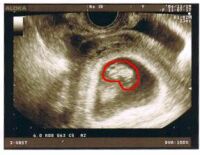

今日超音波で見たら、2cm の勾玉のようになってました。でも心臓が動いているのを見て感動〜!でも血液検査で、5本分も採られて、会計が2万円以上(21950円)だったことにびっくり!血液検査は例の「割引券」が使えるのに、この値段ということで、予想外の高さでした。。

今日の勾玉の状態が「パックマンみたい」ということで、「ぱっくん」と呼ぶことにしました。